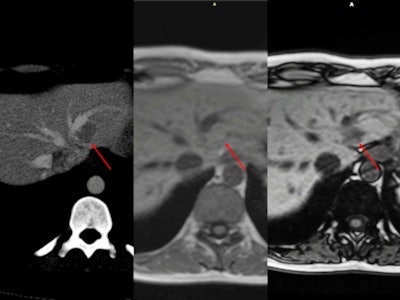

Multifocal fatty liver with no obvious relationship to vascular flow. CT scan shows multiple regions of hypoattenuation on unenhanced CT and portal phase (arrow). When the same patient underwent an MRI scan for follow-up, there was no restricted diffusion. Gradient-echo imaging demonstrates intracellular fat with a drop of signal on out-of-phase images.

Multifocal fatty liver with no obvious relationship to vascular flow. CT scan shows multiple regions of hypoattenuation on unenhanced CT and portal phase (arrow). When the same patient underwent an MRI scan for follow-up, there was no restricted diffusion. Gradient-echo imaging demonstrates intracellular fat with a drop of signal on out-of-phase images.Peliosis hepatis is a rare entity characterized by blood-filled cystic cavities (< 1 mm to several cm in diameter) distributed randomly throughout the liver. First described in patients with advanced cancer and tuberculosis and users of anabolic steroids, its imaging findings vary with the size of lesions, presence or absence of thrombus within the cavities, and presence of hemorrhage, they added. The microscopic form has no specific characteristics.